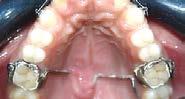

Se describe un caso clínico de un paciente de 14 años y 8 meses, diagnosticado con clase II esquelética, hiperdivergente, clase II molar dere cha, clase I molar izquierda, la relación canina no determinable, el overbite disminuido, el overjet aumentado, con apiñamiento moderado. Con los dientes 12 y 22 palatinizados, el 13 ectópico, con mordida abierta anterior, las líneas medias desviadas, con habito de empuje lingual. Obje tivos: mejorar el perfil facial, corrección del api ñamiento maxilar y mandibular, incorporar al arco los dientes 12,13, 22 y 23, mantener clase I molar izquierda, obtener clase I molar derecha, y canina bilateral, corrección de overjet y over bite, de las líneas medias dentales. Mejorar las relaciones esqueléticas, lograr correcta intercus pidación, la guía de desoclusión canina, la guía incisiva. Mejorar la salud periodontal. La apa ratología utilizada una rejilla lingual de Justus, brackets prescripción Roth 0.022x0.028, tubos bondeables 6´s y 7´s superiores e inferiores. Adicionalmente se realizó ameloplastía en los incisivos anteriores, extracciones de los prime ros premolares superiores, segundos premolares inferiores, terceros molares superiores e inferio res. La retención se llevó a cabo por medio de retenedores circunferencial superior con perla de Tucat y termoformado inferior. El tiempo de tratamiento fue de 2 años y 2 meses.

Paciente de 14 años y 8 meses, moti vo de consulta: “mi mordida no me gusta” el patrón esquelético es cla se II, hiperdivergente, clase II molar derecha y clase I molar izquierda, los caninos superiores en infraoclusión overbite disminuido, apiñamiento severo superior, moderado inferior, con los dientes 12 y 22 palatinizados, el 13 ectópico, con mordida abierta anterior, y las líneas medias desvia das.

hacia la derecha y la línea media dental inferior a la izquierda, con mordida abierta anterior, el canino superior derecho se encuentra fuera del arco ( Figura 3 ), en la oclusal superior los inci sivos laterales palatini zados y paladar ojival profundo, en la lateral derecha una relación molar clase II y relación canina no determinable (Figura 4), en la izquier da una relación molar clase I y relación canina no deter minada.

Para lograr la corrección del apiña miento maxilar y mandibular, se rea lizó la extracción de los OD 14, 24, 35 y 45, para la alineación y nivela ción, se realizó un bondeo seccional superior y secuencia de arcos nitinol 0.014, 0.016, 0.018, 0.017 × 0.025, superior e inferior y acero 0.018,

0.020 superior e inferior. Se incor poraron los OD 13, 23 12 y 22, para obtener clase I canina bilateral se utilizaron elásticos intermaxilares vector clase I 3/16 2.5 oz. para incor porar dientes 12 y 22 se realizó una mecánica de doble arco, para obte ner clase I molar derecha y mante ner clase I molar izquierda se utilizó anclaje mínimo con ligadura de acero 0.012 sector anteroinferior y cadena intramaxilar 43-47 y 33-37 por vesti bular y lingual, para la corrección del overbite el control vertical y manejo del hábito se utilizó una trampa de

Justus (Figura 7) e incorporación de aparatología fija diferenciada 1 mm más gingival en anterior y 1 mm más oclusal en posterior y dobleces esca lonados en nitinol 0.017 × 0.025, en la corrección del overjet se realiza ron topes funcionales en los órganos dentales 16, 26, 36 y 46 ayudando a un posicionamiento anterior man dibular.